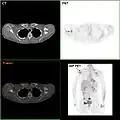

As seen on the image above the breast is already affected with cancer

An illustration of breast cancer